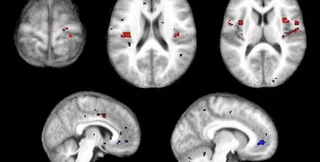

Получить объективные данные о болевых ощущениях ученым позволила комбинация методов Функциональной магнотно-резонансной томографии и особого "самообучающегося" программного алгоритма, сообщает compulenta.ru.

Когда человек что-то видит, слышит и вообще чувствует, у него активируются определенные участки мозга, которые можно обнаружить посредством ФМРТ. Более того, по активности мозга реально предсказать характер ощущений, не зная ничего о том, что именно их вызвало. Информацию о схеме активности можно внести в программный алгоритм, который и будет распознавать ощущения по картинке, сообщаемой ФМРТ.

В эксперименте стэнфордских ученых участвовали восемь добровольцев. Каждому предстояло испытать легкий термический ожог: участок кожи нагревался до тех пор, пока тепловые ощущения не переходили в болевые. Компьютер регистрировал изменения в активности мозга и вычленял общие черты у всех участников эксперимента. После выявления болевого алгоритма исследователи проверили его на 16-ти новых добровольцах, и оказалось, что метод позволяет отличить боль от неболи более чем в 80% случаев.